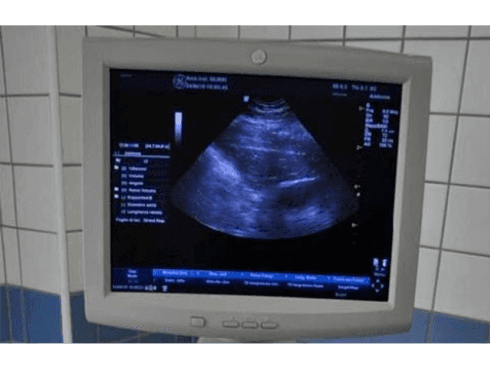

- ecografie - ecodoppler;